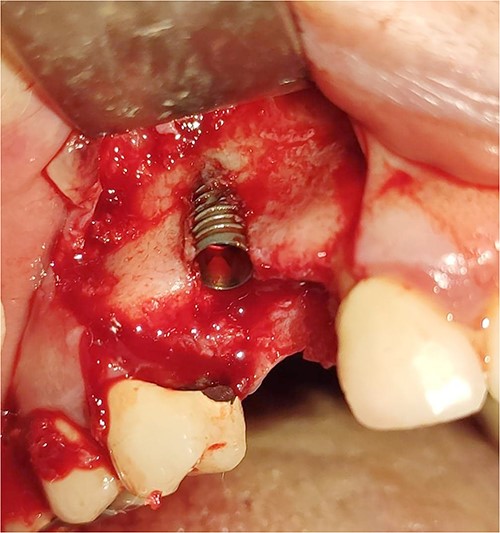

Under local anesthesia with 4% articaine solution, a full-thickness flap was raised to expose the alveolar ridge. The initial point was marked with a point drill. The implant site was first prepared with a 2.2 mm pilot drill, and then with a 3.3 mm drill. After preparing the implant bed, we noticed the disappearance of the coronal and middle third of the buccal wall, exactly as planned. A submerged implant system (INNO submerged implant; Cowellmedi Inc, South Korea) was inserted according to the manufacturer’s instructions (Fig. 1). The insertion torque value was 33 N.cm. several perforations were prepared at the buccal side of the recipient bone bed using a small round bur for better blood supply. An allogeneic bone graft material (Cortical Cancellous powder; TRCIR Co, Iran) was used to reconstruct the buccal plate. A prefabricated L-shaped titanium mesh has been adapted to fit the shape of the alveolar ridge to be reconstructed, and it was fixed to the implant with a cover screw (Fig. 2). The flap was mobilized to permit a tension-free primary closure, was closed with 4–0 silk sutures. Sutures removal was done after 1 week. The surgical sites were left to heal for 6 months.

Inserting a dental implant of 3.5 mm diameter and 10 mm length into its prepared bed. The implant was completely surrounded by bone in its apical third only.